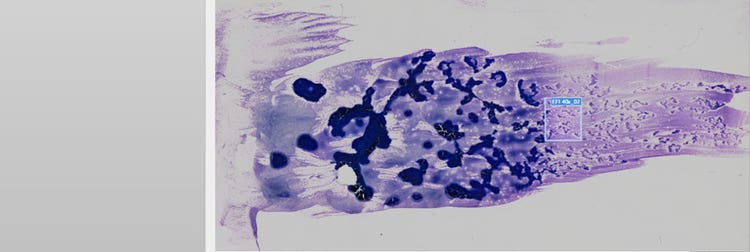

Procesamiento de imágenes de portaobjetos completos de una muestra de sangre periférica

Figura 1. Muestra de sangre periférica humana de una leucemia aguda promielocítica, escaneada con el escáner de portaobjetos dedicado a la investigación VS200. Imágenes por cortesía de Jana Kirsten, Instituto de Química Clínica y Medicina de Laboratorio del Centro Médico Universitario de Regensburg.

En esta aplicación, la sangre periférica muestra los promielocitos neoplásicos con núcleos bilobulados o gránulos extremos (Figura 2, flecha naranja). Estos promielocitos neoplásicos también se hallan en la médula ósea, así como en las células blásticas mieloides en las que se hay haces completos de bastones de Auer (flecha verde en A, B y C). Es importante tenerlos en cuenta si se sospecha una APL.